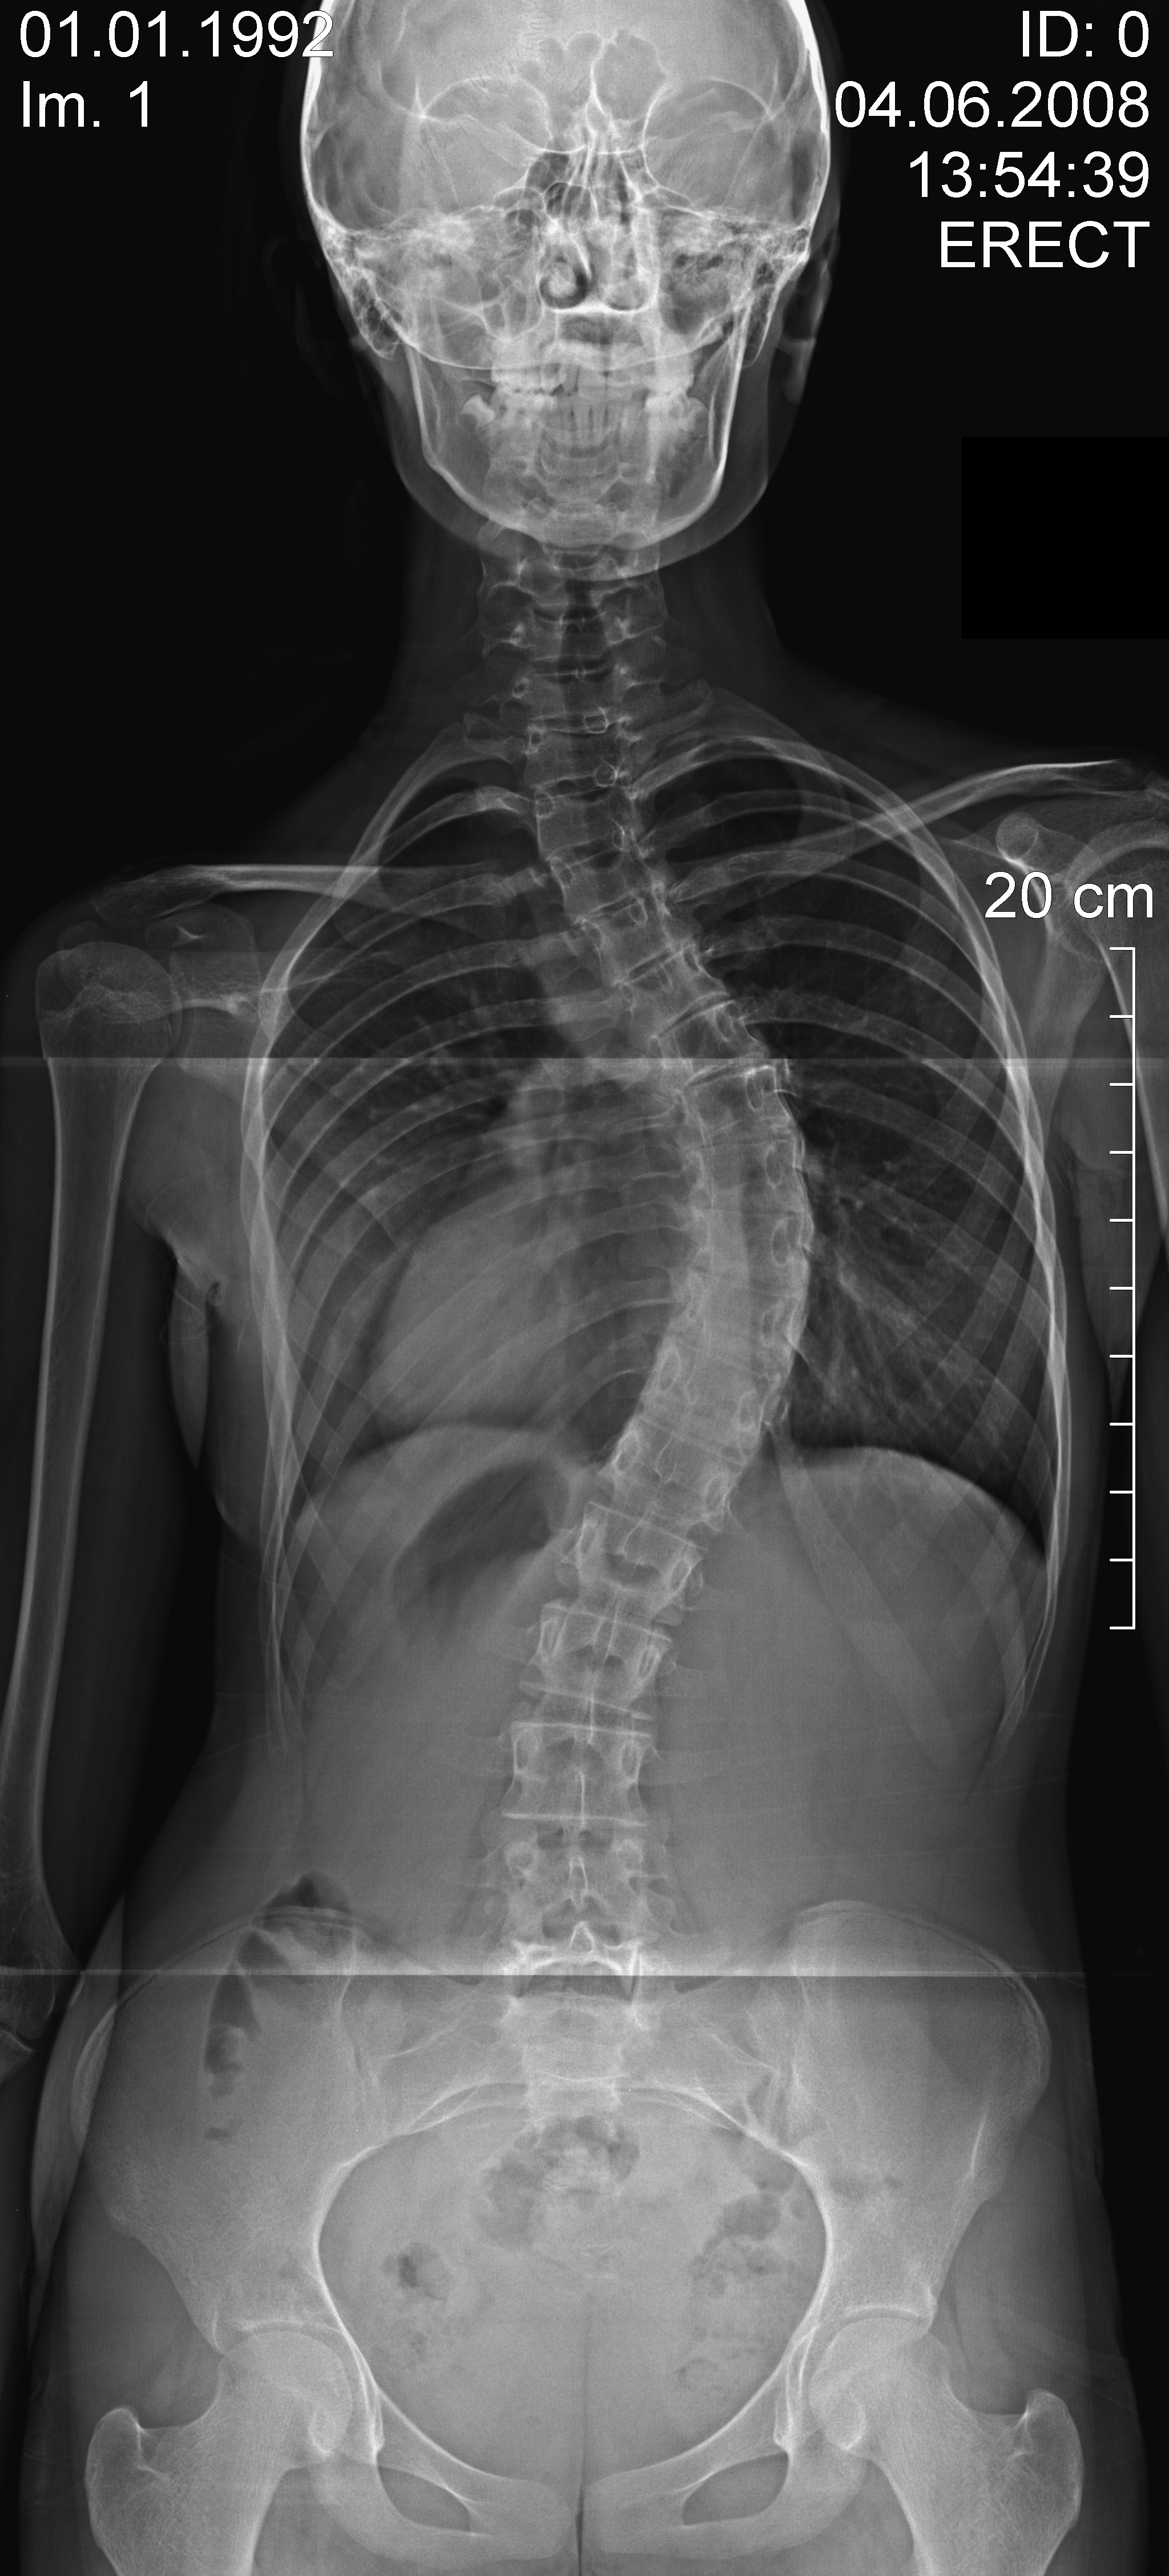

Cerrahiden önce özel eğilmeli ya da traksiyon filmi denilen özel röntgen filmleriyle skolyoz eğriliğinin ne düzeyde esnek olduğu anlaşılmaya çalışılır. Ameliyatı yapacak olan cerrah bu filmlerle ölçüm yaparak esneklik hakkında fikir sahibi olur. Skolyoz eğriliği ne kadar esnekse o kadar çok düzelme elde edilir.